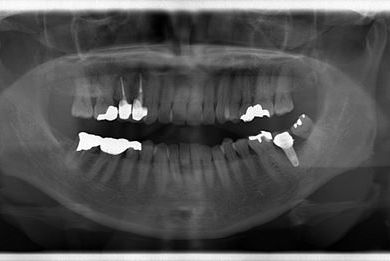

インプラント治療+セラミック治療

| カテゴリー | 【インプラント治療】【セラミック治療】 | ||||||||||||||||||||||||||||||||

| 性別/年齢 | 女性 / 61歳 | ||||||||||||||||||||||||||||||||

| 主訴 | 奥歯がぐらつく。 | ||||||||||||||||||||||||||||||||

| 治療方針 | インプラント治療にて機能的・審美的回復を行う。 | ||||||||||||||||||||||||||||||||

| 治療内容 | インプラント1本、メタルボンドセラミッククラウン3本(メタルボンドセラミック用土台2本) | ||||||||||||||||||||||||||||||||

| 総治療費 | 625,538円 | ||||||||||||||||||||||||||||||||

| 治療期間 | 1年0ヶ月 |